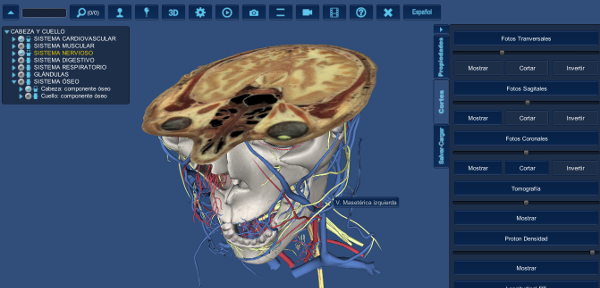

5.Observe la ventana de

Interacción.

Puede realizar cortes en los

tres ejes anatómicos simultáneamente.